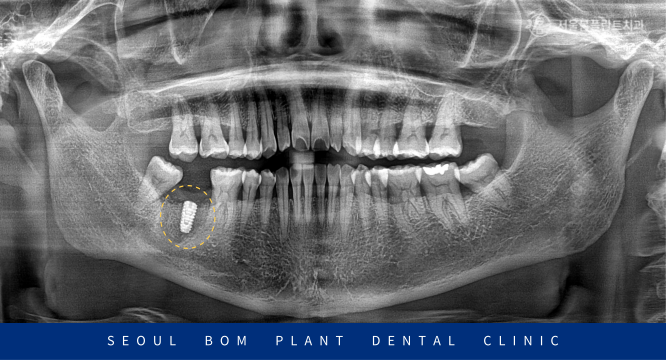

이 환자분의 상태를 정밀하게 검사하기 위해

파노라마 촬영을 진행한 결과,

아래턱 오른쪽 두 번째 어금니(#47) 주변에

심각한 염증이 확인되었습니다.

이 염증이 하치조 신경관까지 영향을 미쳐,

방치할 경우 주변 조직과 다른 치아에까지

영향을 미칠 수 있는 위험한 상황이었습니다.

뼈이식 2달 후, 파노라마 촬영을 통해

발치 부위에 하얗게 뼈가 차오른 것을 확인한 후,

임플란트 식립을 진행하였습니다.

오금역치과 서울봄플란트에서는 임플란트 식립 전,

파노라마와 3D CT 촬영을 통해 환자의

구강 상태를 꼼꼼하게 검진했습니다.